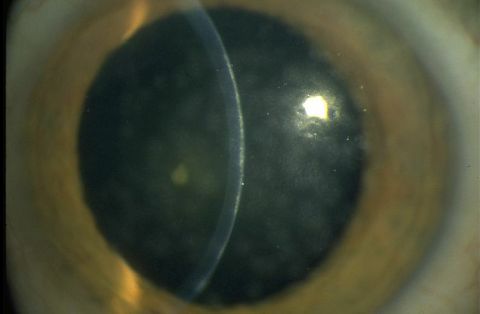

- Epithelial keratitis

- Subepithelial infiltrates

Conjunctival inflammation can progress to focal epithelial keratitis, and the resulting lesions can last for up to 2 weeks. After this period, subepithelial infiltrates (also known as “nummuli”), which are thought to be related to the immune response, can form beneath the lesions. Nummuli occur at approximately day 10 and can give rise to irregular astigmatism and photophobia. These symptoms and decreased visual acuity can persist for months or years.[5][11][12]